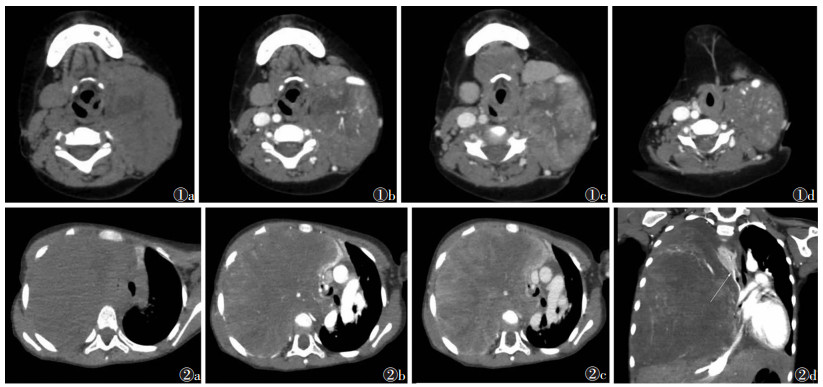

2 结果7例均为单发,位于右颈部3例,左颈部2例(图 1),右胸腔(图 2)及左胸壁各1例;肿块大小3.2 cm×4.5 cm×6.7 cm~10.0 cm×12.4 cm×16.8 cm;3例呈团块状,2例呈卵圆形,2例形态不规则;6例边界清晰,1例边界模糊。CT平扫4例密度较均匀,稍低于同层面肌肉密度(图 2a),2例呈不均匀等低密度,内部伴条片状或不规则液化坏死(图 1a),1例伴斑片状出血而呈等高密度,7例均未见脂肪成分及钙化。增强扫描动脉期肿块实性部分不均匀强化(图 1b,2b,2d),其中3例可见增粗迂曲血管穿行,静脉期肿块呈持续片絮状、团片状及斑马纹状强化(图 1c,2c),延迟期强化减弱。1例伴下颌骨轻微溶骨性破坏,1例侵犯喉咽,1例伴腋窝淋巴结转移(图 1d)。

| 图 1 男,9岁,横纹肌肉瘤(RMS) 图 1a 平扫左颈部见卵圆形等低密度肿块,内部伴条片状液化坏死,边界清晰 图 1b 动脉期不均匀强化,内部可见粗大血管 图 1c 静脉期呈持续团块状强化,左侧喉咽受侵增厚 图 1d 动脉期肿块前方伴肿大淋巴结影,强化不均匀,边界不光滑 图 2 男,4岁,RMS 图 2a 平扫右胸腔见团块状稍低密度肿块,边界较清晰 图 2b 动脉期不均匀强化,内部伴较粗大血管 图 2c 静脉期呈持续斑马纹状强化 图 2d 动脉期冠状位显示肿块巨大,相邻肺组织受压不张(长箭),纵隔受压左移 |